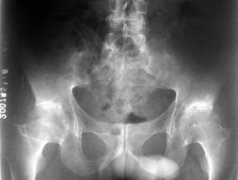

强直性脊柱炎检查

• 强直性脊柱炎检查常用三种方法